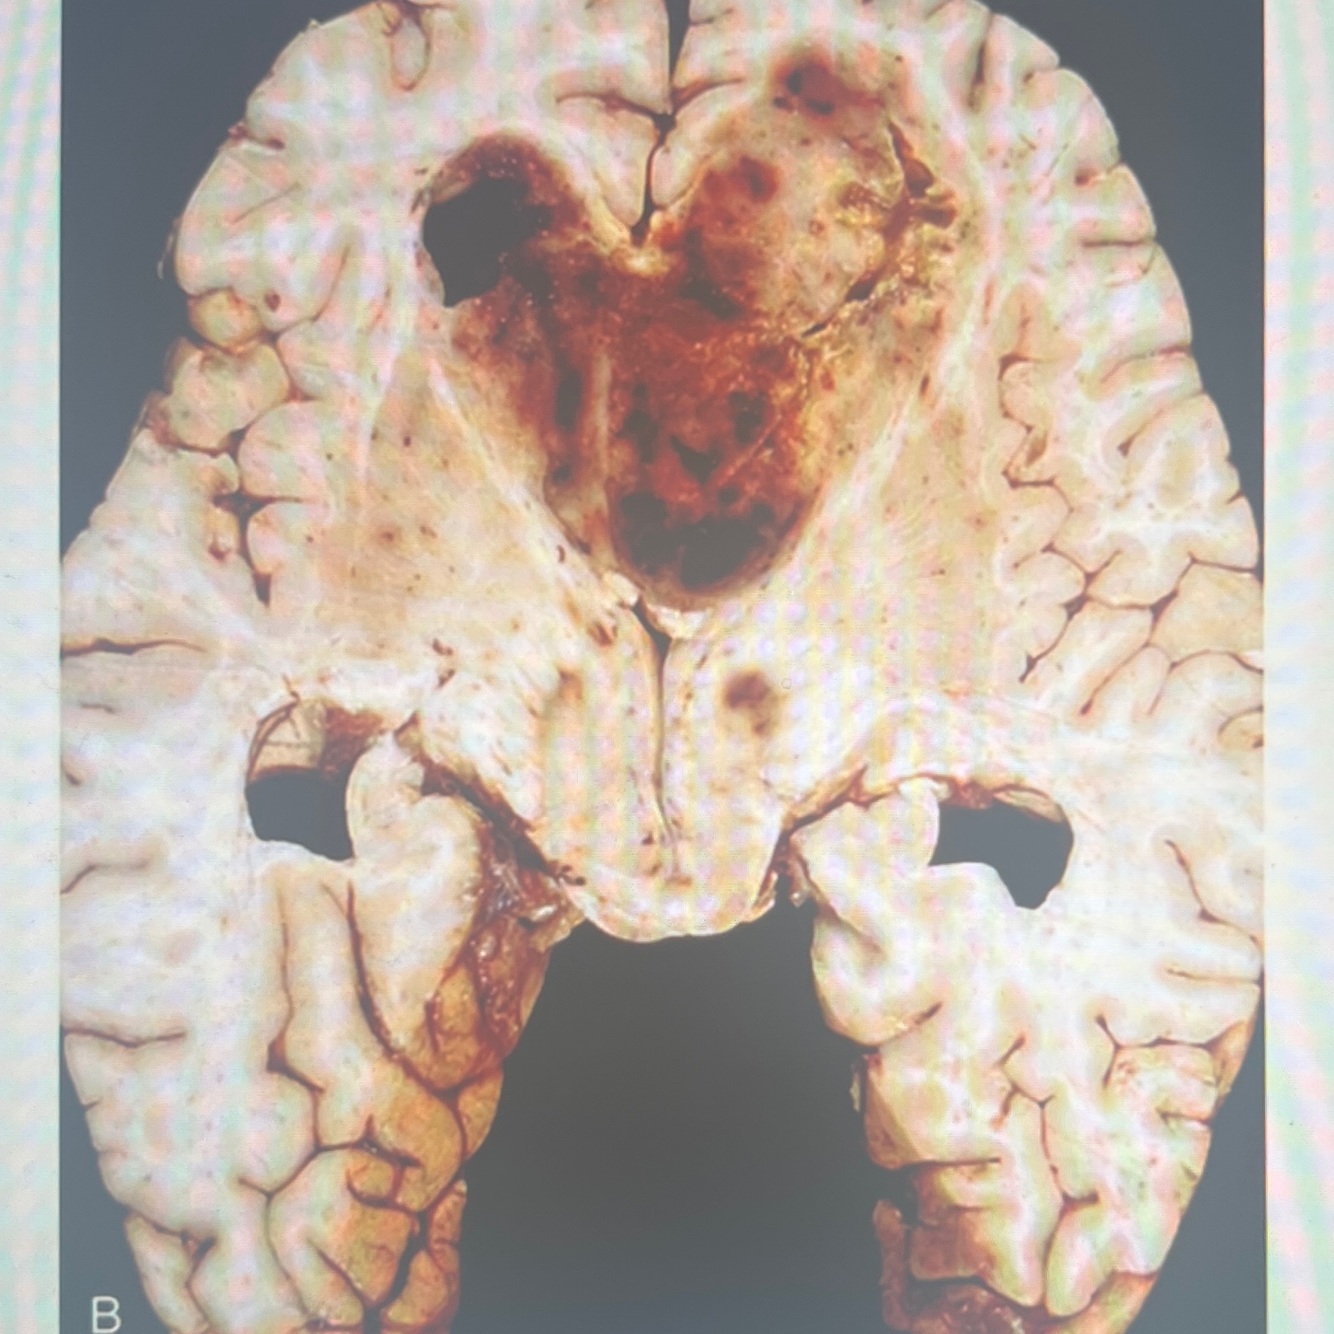

Diagnosis: intraventricular hemorrhage

Location: lateral and third ventricles

A coronal section in the brain showing a collection of blood in the subependymal region and within the lateral and third ventricles in a premature newborn

The brain parenchyma is compressed